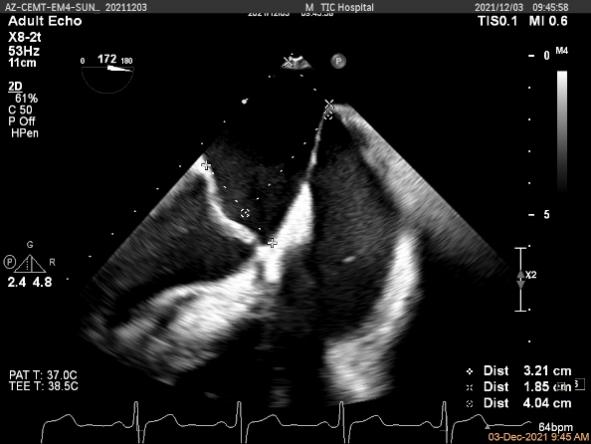

X-plane:下夹子尝试先捕获1区脱垂瓣叶

夹子关闭过程中,Color提示1区反流逐渐减少

二尖瓣口平均跨瓣压差:2mmHg

肺静脉血流频谱恢复正向